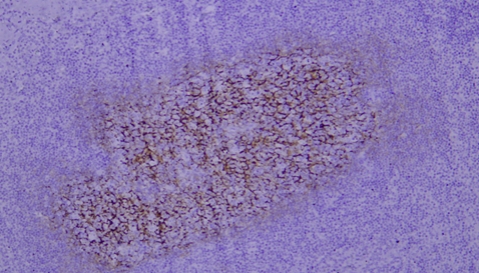

Typical Example:CD34 staining of paraffin-embedded human placental tissue sections:

HRP-directly labeled secondary antibody: Weak positive staining with low background;

Polymer enzyme-labeled secondary antibody: Strong positive staining with clean background and distinct contrast.

Conclusion: Different chromogenic systems yield distinct chromogenic results. Polymer enzyme-labeled secondary antibodies demonstrate higher sensitivity, cleaner background, and more distinct contrast compared to conventional HRP-directly labeled secondary antibodies.